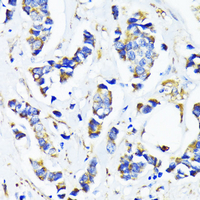

Immunohistochemical analysis of MRPL45 staining in human breast cancer formalin fixed paraffin embedded tissue section. The section was pre-treated using heat mediated antigen retrieval with sodium citrate buffer (pH 6.0). The section was then incubated with the antibody at room temperature and detected using an HRP conjugated compact polymer system. DAB was used as the chromogen. The section was then counterstained with haematoxylin and mounted with DPX. -